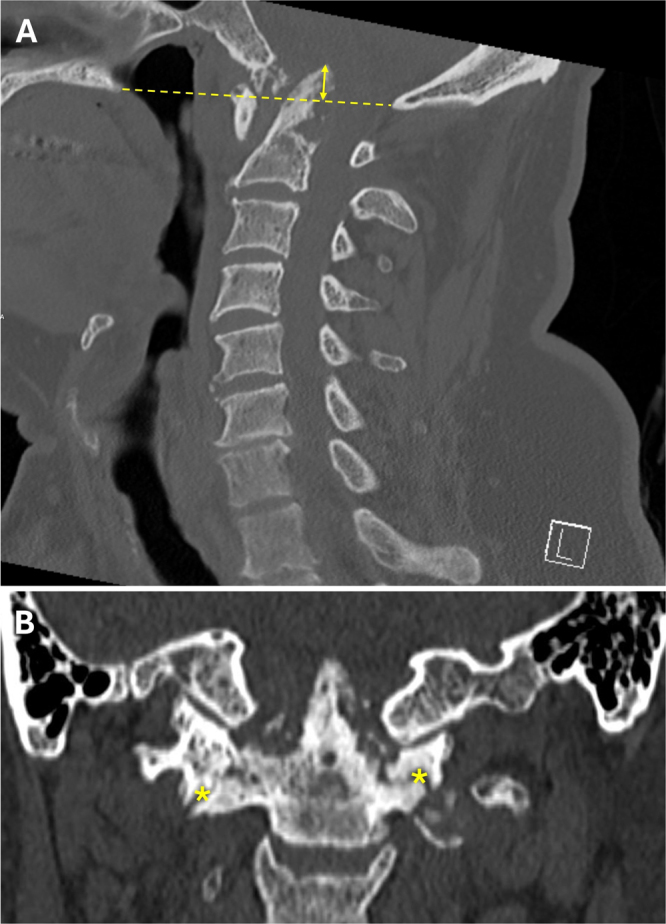

Background: Calcium pyrophosphate dihydrate (CPPD) deposition disease at the craniocervical junction (CCJ) typically presents with a retro-odontoid pseudotumor. Here, the authors report a case of CPPD-induced basilar impression, causing vertebral artery (VA) dissection and hemorrhage.

Observations: A 65-year-old male presented with worsening chronic cervicalgia, occipital headaches, and unstable tandem gait. CT revealed basilar impression with severe atlantoaxial erosion and instability, absent on imaging 8 months prior. MRI showed high-grade CCJ stenosis without myelopathy, due to CPPD. Before treatment could be initiated, the patient was suddenly found unresponsive. CT showed posterior fossa hemorrhage due to VA dissection, with secondary obstructive hydrocephalus. An external ventricular drain was placed, followed by coil VA embolization. After halo vest placement, CCJ alignment was restored and the patient underwent occipitocervical fusion. Following prolonged rehabilitation, he regained independent living without significant neurological sequelae.